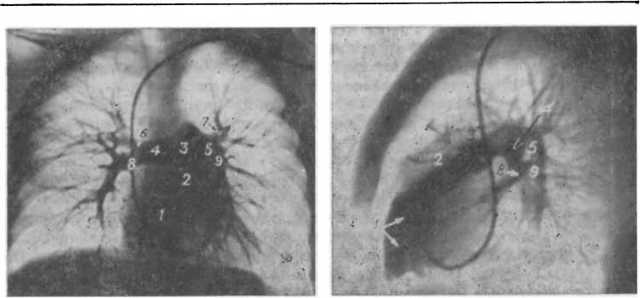

Материалы публикуются для ознакомления, и не являются предписанием к лечению! Рекомендуем обратиться к врачу-гематологу в вашем лечебном учреждении! Соавторы: Марковец Наталья Викторовна, врач-гематолог Легочная артерия